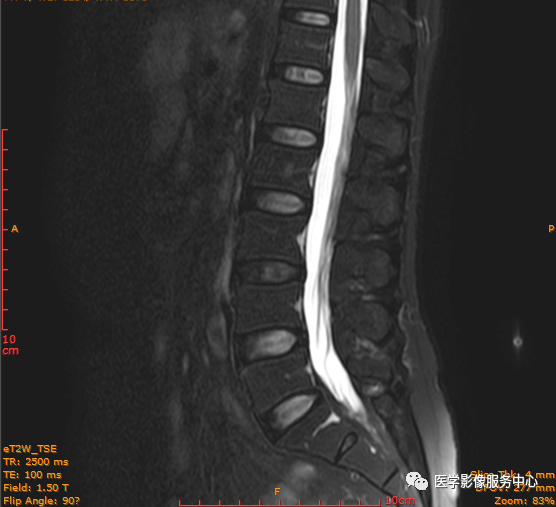

临床诊断 :腰突症?故行腰椎MRI检查,图像如下:

T1矢状位

影像表现主要在T2矢状位及T2横断位可见椎间盘前缘或后缘可见高信号区;

日常工作因腰腿疼痛来检查腰椎MRI的很多,而腰腿疼痛并不一定就是腰椎椎间盘突出或膨出导致的,我们应该需要知道椎间盘HIZ也会引起腰腿疼痛,这种椎间盘源性的疼痛我们不能“忽略”;椎间盘后方HIZ并不少见,椎间盘后方 HIZ 在 T2WI 的局限性高信号、T1WI 呈局限性较低或等信号意味着通常所指的纤维环破裂伴随肉芽组织长入;而 T1WI、T2WI 均呈高信号可能是钙化组织。